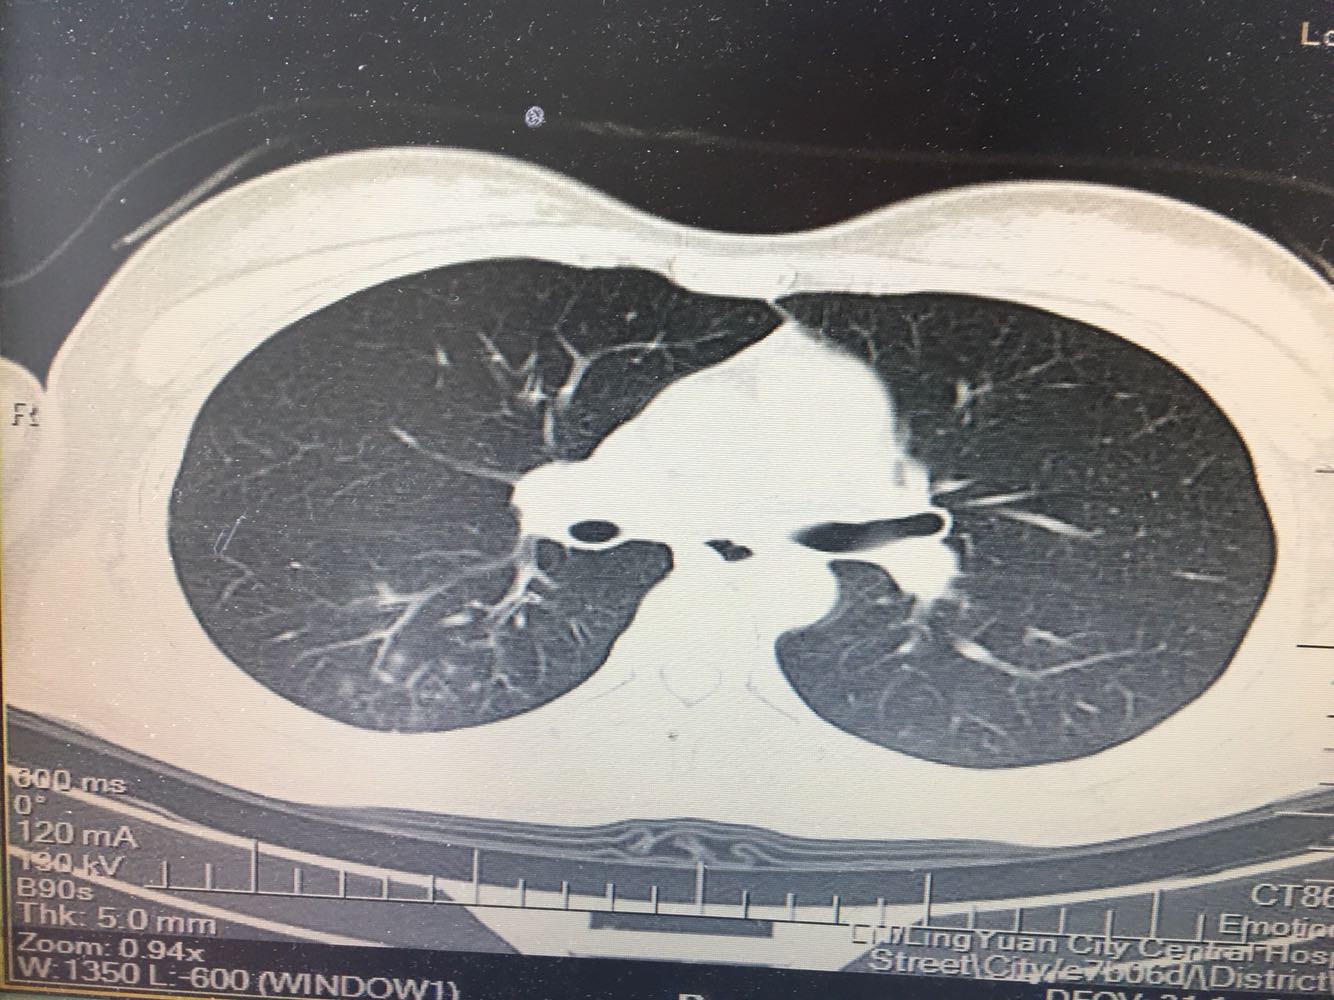

支原体肺炎?肺结核?

女,26岁,咳嗽1周,咳痰不畅,咽喉痒,口服阿莫西林无好转,昨日发热,体温38.5摄氏度,于门诊查肺CT后以肺炎收入院,病来无盗汗,无咳血,无消瘦及乏力,无头痛,无肢体酸痛,饮食睡眠可,二便正常

支原体抗体1:160,结核抗体弱阳性。支原体肺炎个别可见上叶病变,该患无结核中毒症状,考虑支原体肺炎可能性大,但肺尖为结核好发部位,需要抗炎治疗后复查观察疗效。